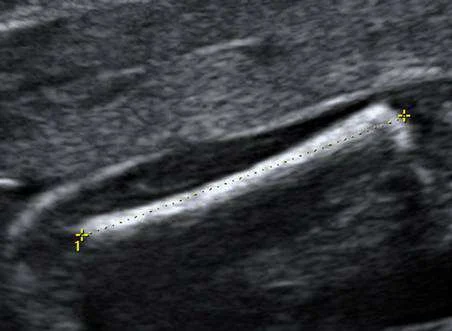

【108-2 醫學(六) 第32題】45歲孕婦,G5P4,妊娠週數不明,接受產科超音波檢查,正在測量標的的名稱(雙十字之間)為何?

詳解

破題關鍵

這張超音波影像顯示的是胎兒的一根長骨,測量標記(雙十字)精準地量測了這根骨頭的長度,這是典型的股骨長度(FL)測量。

選項拆解

-A:錯在 BPD(biparietal diameter)是測量胎兒頭部的雙頂徑,影像中並非胎兒頭部。